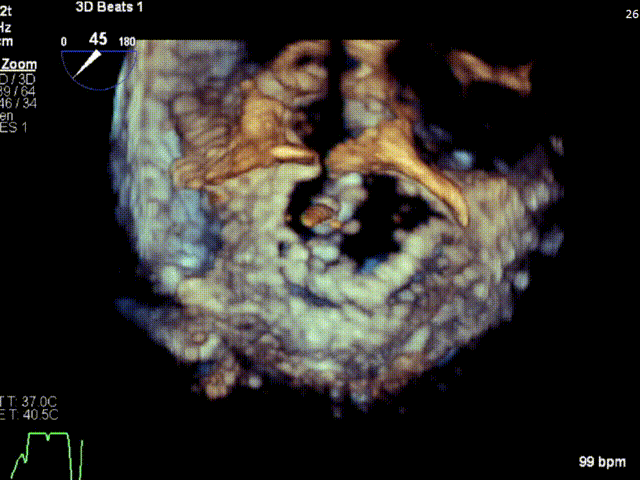

术前3D VIEW

经食道超声提示,患者二尖瓣P1 commissural脱垂、腱索断裂合并重度反流(Carpentier II型/DMR4+)。

二尖瓣后瓣环明显钙化;主动脉瓣轻度钙化;三尖瓣中度功能性反流(FTR2+)。左房明显扩大;左室壁非对称性肥厚,以室间隔基底段肥厚为著(HOCM)。左室整体收缩功能正常。

二尖瓣环AP径33mm,二尖瓣后瓣环明显钙化,房间隔拟穿刺高度40mm;二尖辦脱垂宽度5.7mm,脱垂高度7.7mm,二尖瓣1区前叶长度29mm,后叶长度19mm,二尖瓣2区前叶长度23mm,后叶长度14mm,MVA=4.0cm²。